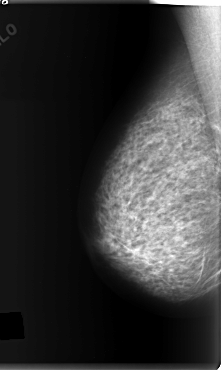

C_0148_1.LEFT_MLO

LEFT_MLO LINES 5896 PIXELS_PER_LINE 3496 BITS_PER_PIXEL 12 RESOLUTION 50 OVERLAY